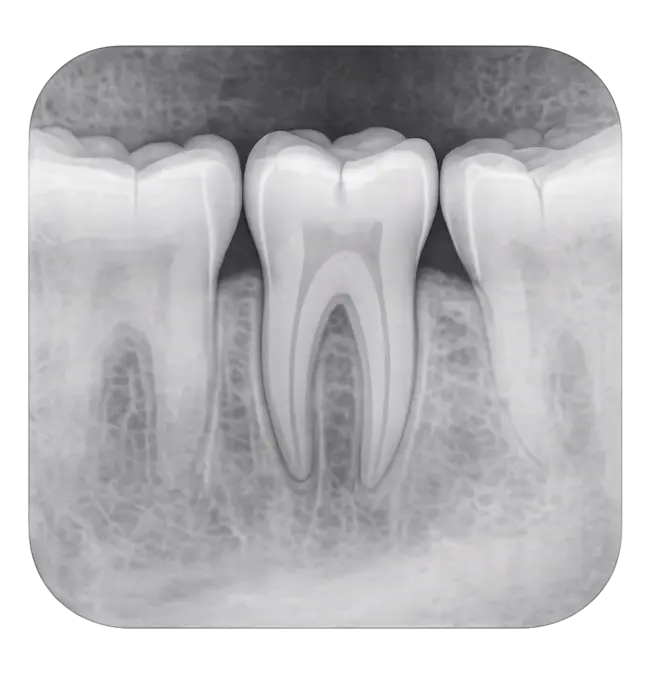

Периапикальный снимок

Это прицельный рентген зуба, который показывает не только видимую часть зуба (коронку), но и корень целиком, а также костную ткань вокруг него. Благодаря этому врач может увидеть даже скрытые проблемы, которые невозможно обнаружить при обычном осмотре.

Что позволяет выявить периапикальный снимок:

- Кариес на труднодоступных участках зуба.

- Воспаление или инфекции в корне зуба.

- Трещины и повреждения зуба.

- Состояние костной ткани вокруг зуба, например потерю или рассасывание кости.

- Ретинированные зубы или аномалии их расположения.